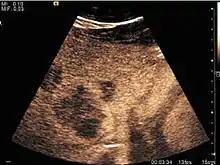

Liver abscess (2D and CEUS). 2D Examination reveals the fluid nature of the mass and imprecise delineation. CEUS examination shows congestion in the surrounding liver parenchyma and excludes a vascular tumor.

Liver abscess have heteromorphic ultrasound appearance, the most typical being that of a mass with irregular shapes, fringed, with fluid or semifluid content, with or without air inside. Doppler examination shows the lack of vessels within the lesion. CEUS exploration shows hyperenhancement during arterial phase close to the lesion, this being suggestive of a liver parenchymal hyperemia. During venous and sinusoidal phase the pattern is hypoechoic, and the central fluid is contrast enhanced. CEUS examination is useful because it confirms the clinical suspicion of abscess. In addition, it allows for an accurate measurement of the collection size and an indication regarding its topography inside the liver (lobe, segment).